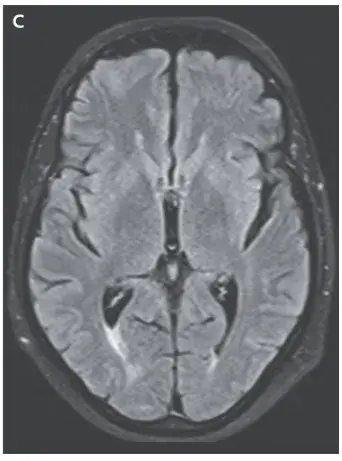

A ressonância magnética (MRI) de crânio ponderada em T2 mostrou sinal hiperintenso na substância branca cortical e subcortical, achados consistentes com **edema vasogênico** (imagens A e B). Os achados da angio-RM arterial e venosa foram normais.

Realizado retirada do medicamento (ciclosporina) e os sintomas do paciente e os achados da ressonância magnética foram resolvidos (Imagem C).